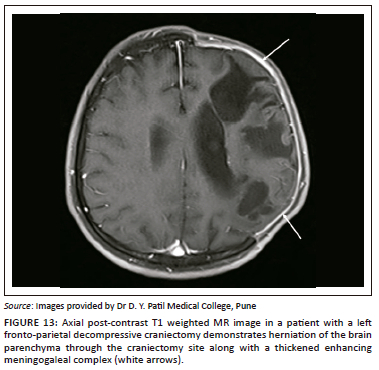

Extracranial herniation

In cases of raised intracranial pressure from any aetiology, such as cerebral oedema or haemorrhage; the oedematous brain parenchyma herniates via the craniectomy defect (Figure 11, Figure 12 and Figure 13). This leads to compression and contusions in the parenchyma at the bony margins of the craniectomy and compression of the superficial cortical veins leading to infarction.16